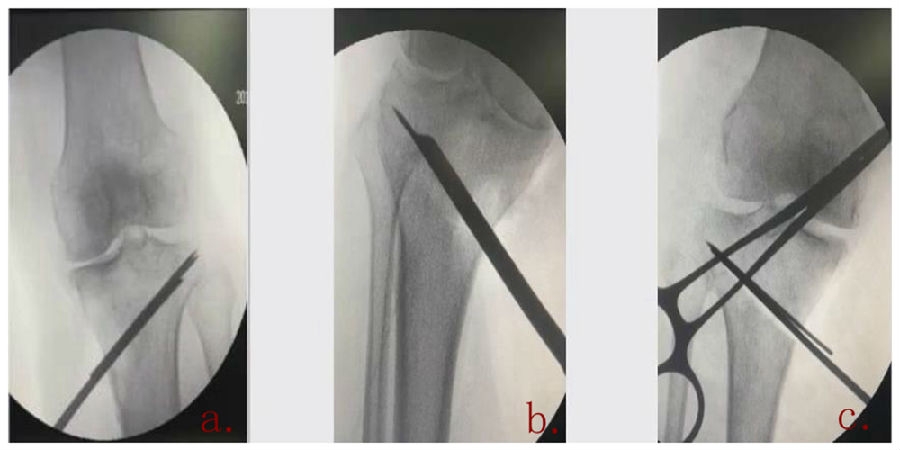

(3)Ⅲ型骨折

首先要把截骨撑开钳拿下来,此时骨折端会自动复位,然后再由外向内侧打入一颗拉力螺钉,将胫骨平台做临时固定,然后再进一步的用摆锯锯或是用骨刀打,保留1cm的合页,最后再进行撑开,做内固定。同样要求患者做结构植骨加延迟负重。

截骨偏前,截骨线过短;Ⅲ型骨折;保留1cm合页

结构植骨,外侧拉力钉固定